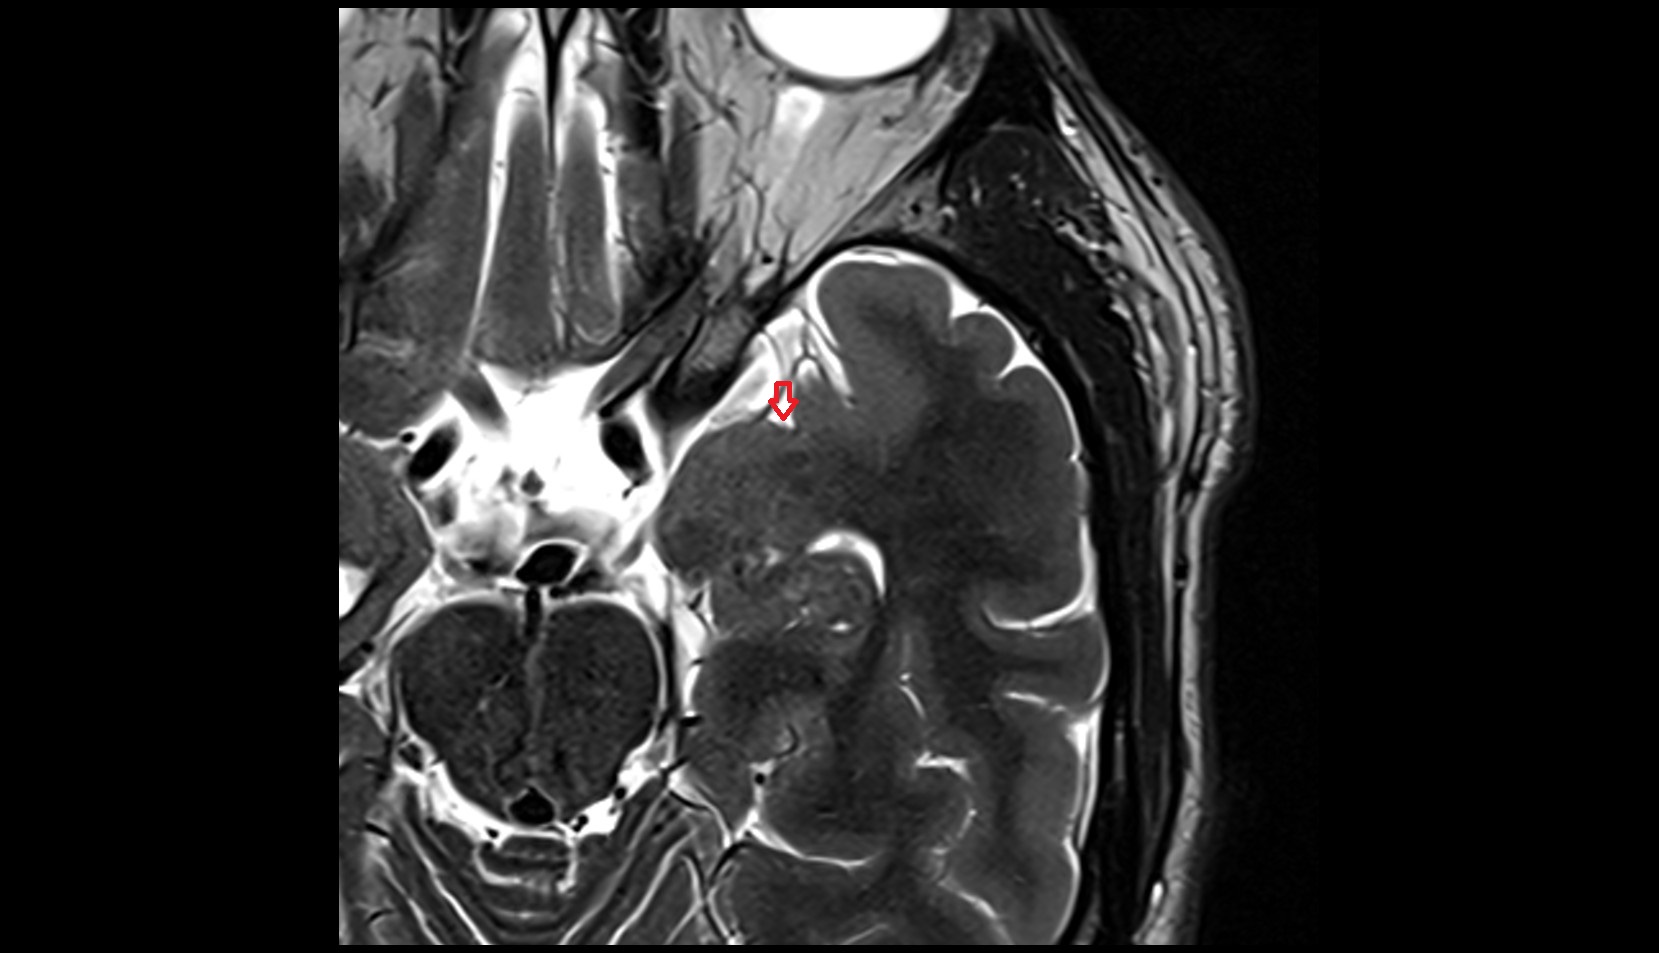

- Fetal brain

- Fetal cerebellum

- Fetal occipital lobe

- Fetal temporal lobe

- Fetal parietal lobe

- Fetal frontal lobe

- Fetal lateral ventricle